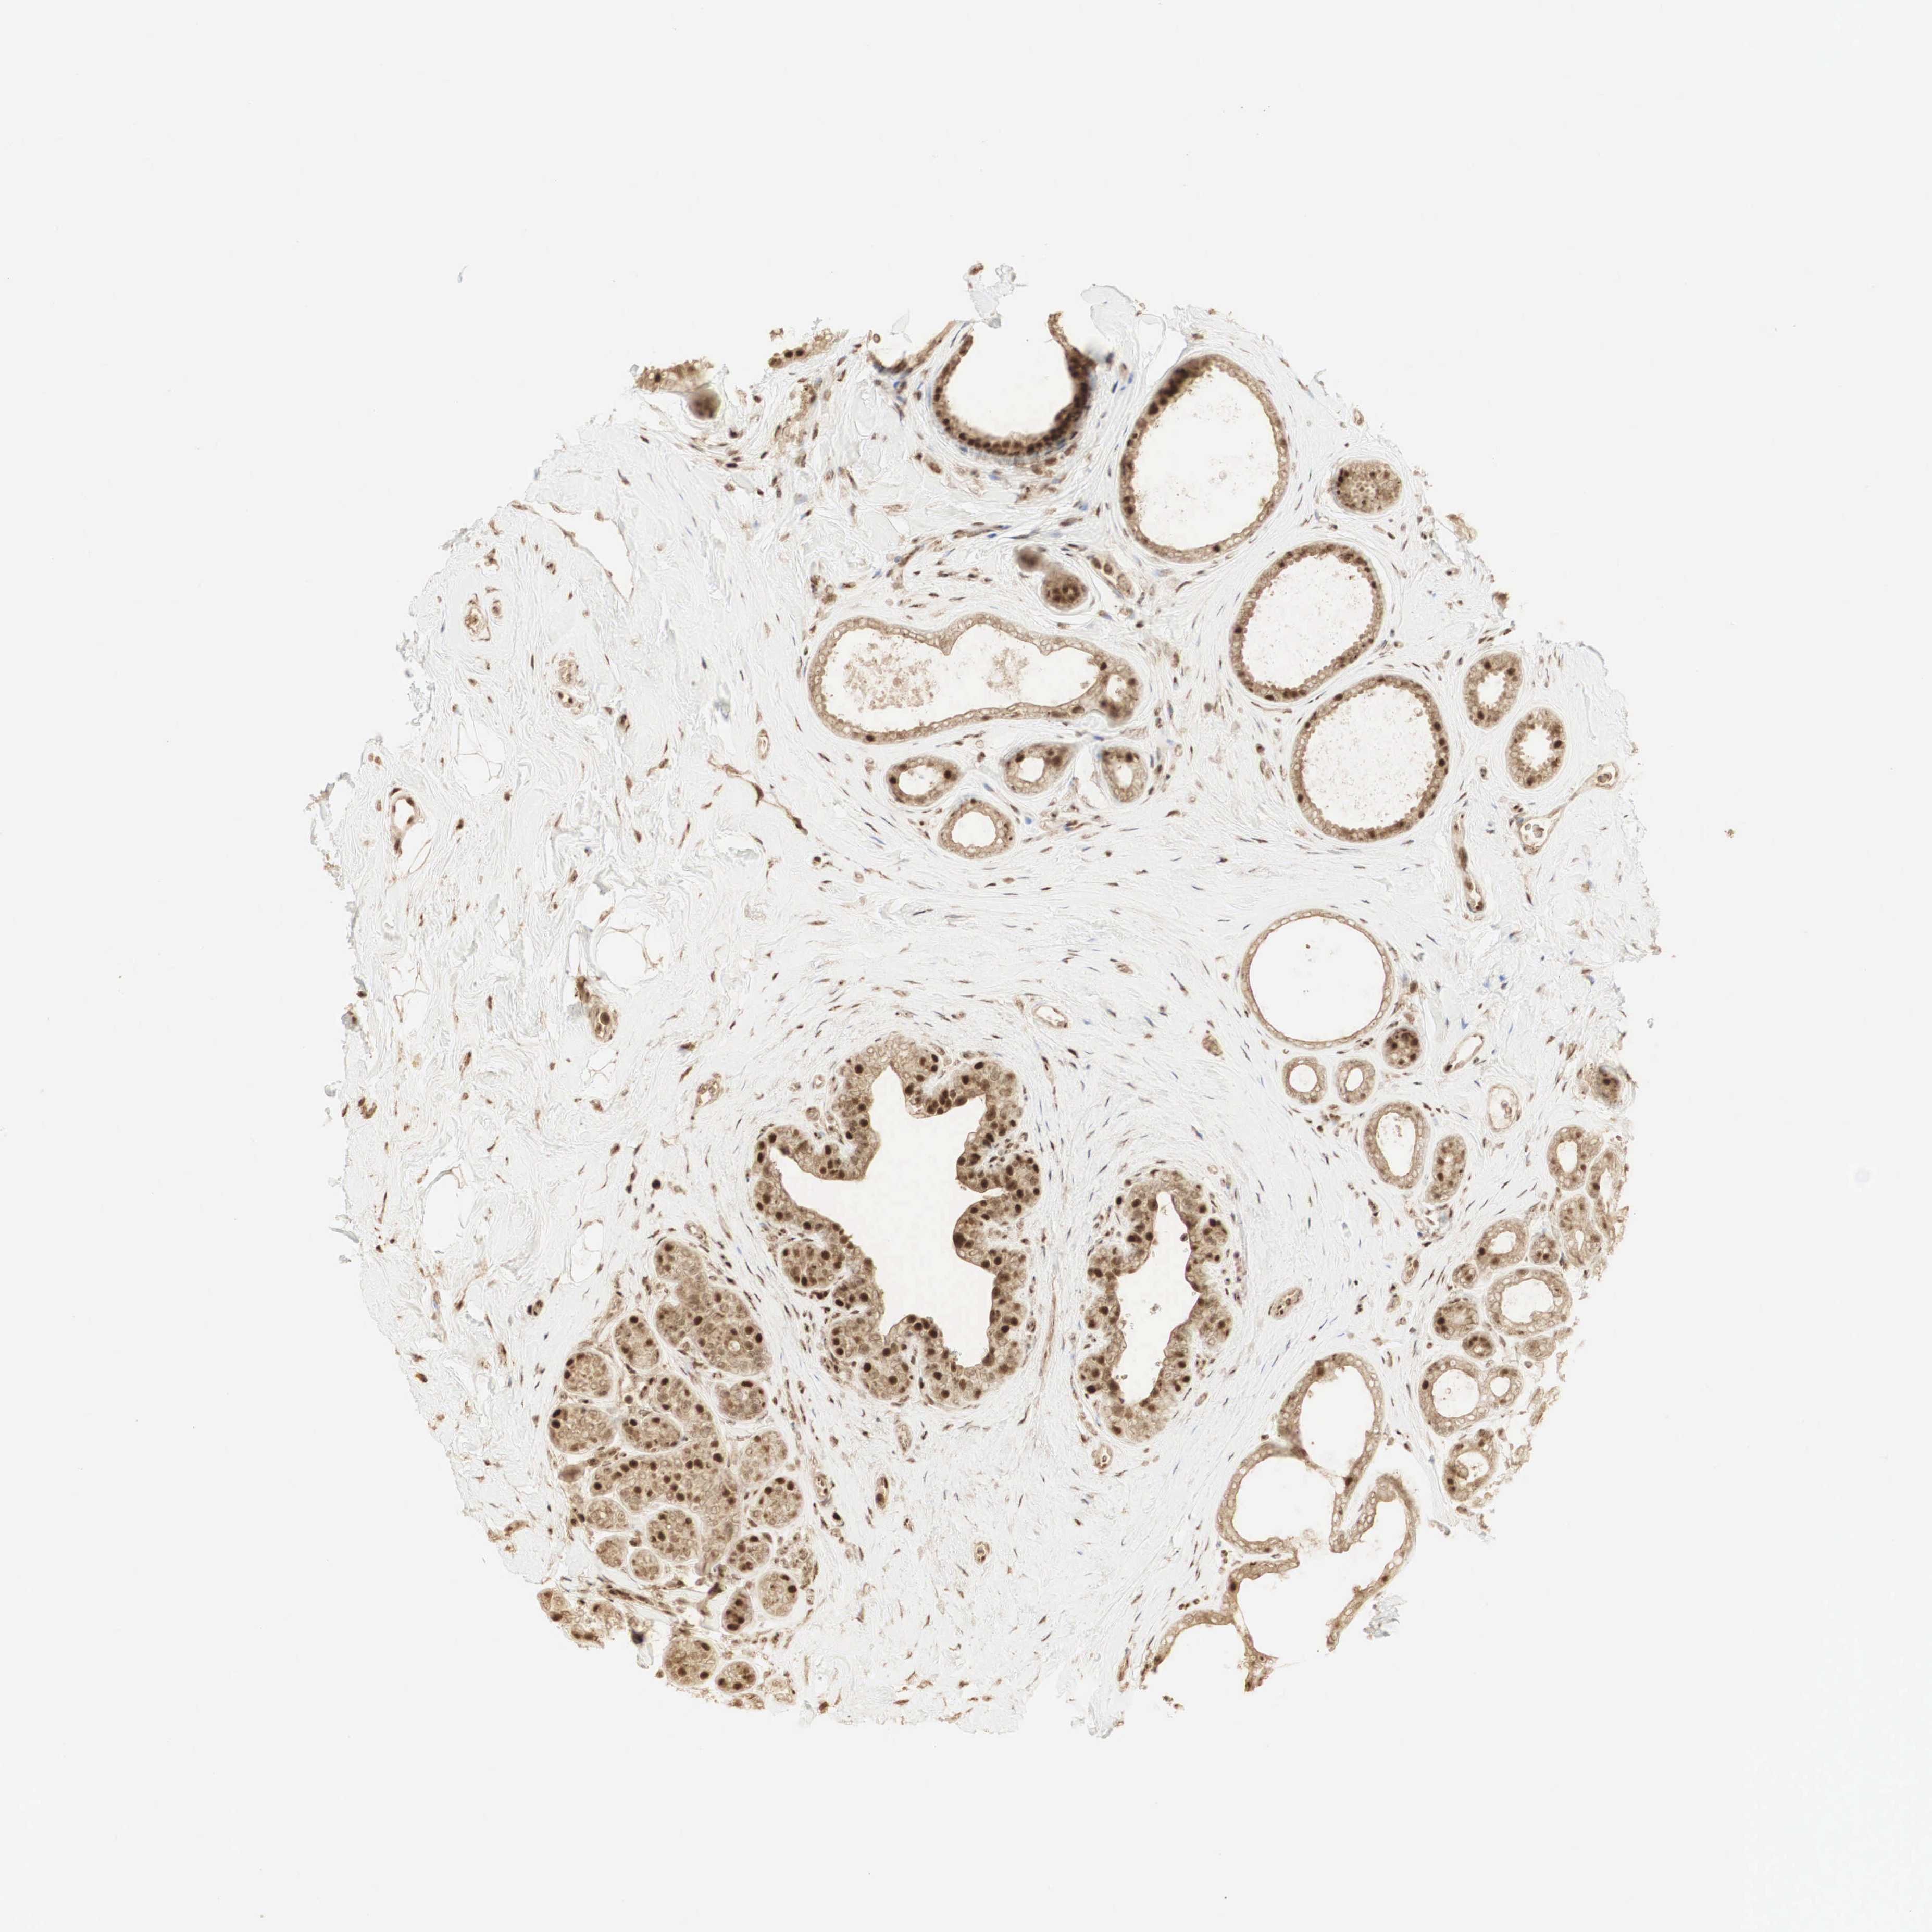

CANCER BREAST CANCER Show tissue menu

BRCA TCGA BRCA VALIDATION PROTEIN EXPRESSION